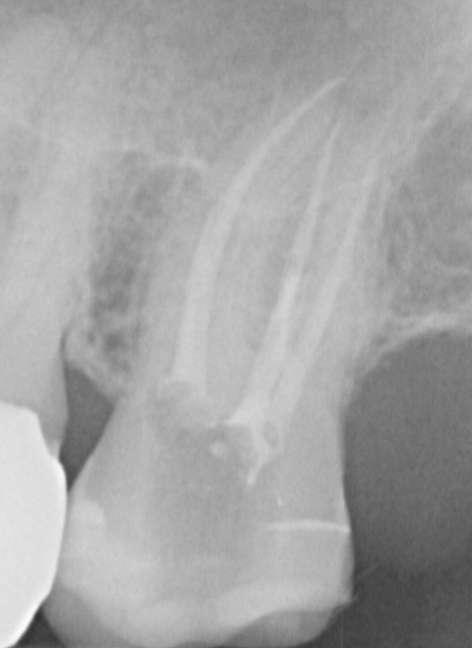

Röntgenologischer Befund: Therapie

Das präoperativ angefertigte diagnostische Röntgenbild zeigt eine insuffiziente Amalgamfüllung im distalen Approximalraum. Die mesiale Wurzel weist eine periapikale Osteolyse auf (Abbildung 1).

Abbildung 1: Präoperative Diagnostische Aufnahme